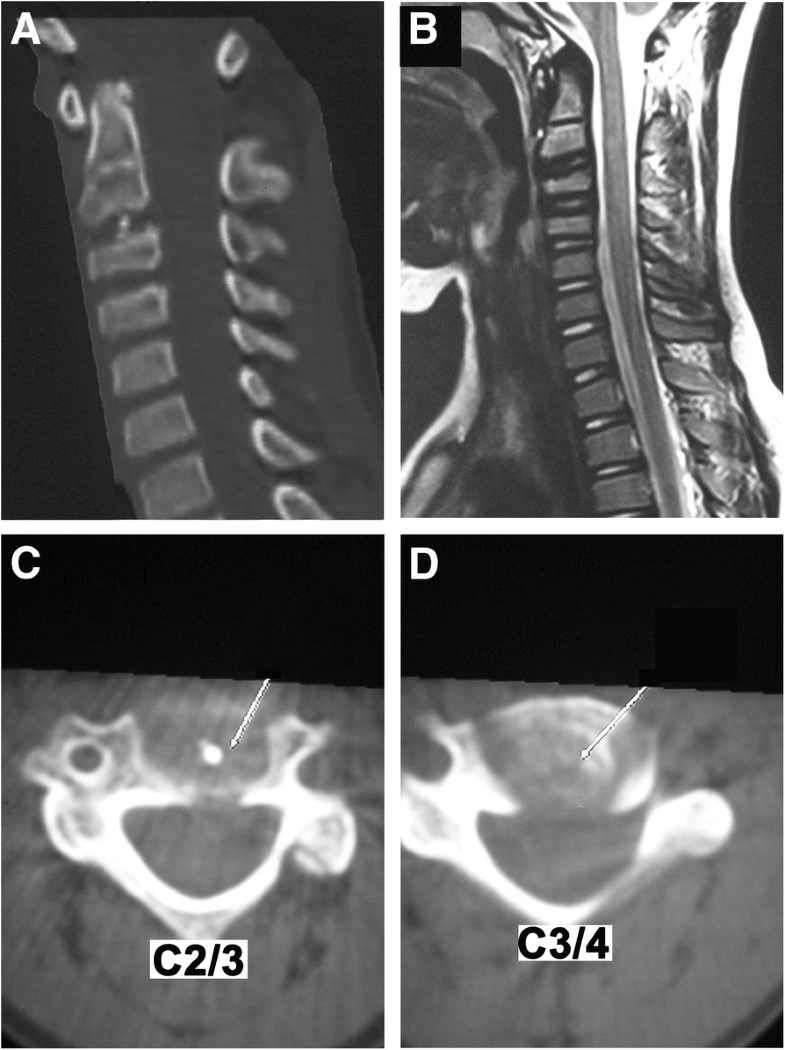

Pediatric idiopathic intervertebral disc calcification of the cervical Intervertebral Disc Calcification Radiology It may be observed in pediatric 5. It is frequently seen as a consequence of disc aging and progressive degeneration but exhibits unique molecular and. Annulus fibrosus calcification is a form of intervertebral disc calcification where the peripheral annular portion (annulus fibrosus) can get calcified. To determine the prevalence, distribution, and location of intervertebral disk calcification (idc) in the. This. Intervertebral Disc Calcification Radiology.

Sagittal CT scan reveals a regular oval calcification within the C2/C3 Intervertebral Disc Calcification Radiology It may be observed in paediatric 5 as well as adult populations. Intervertebral disc (ivd) calcification is associated with ivd degeneration and can lead to pain. Annulus fibrosus calcification is a form of intervertebral disc calcification where the peripheral annular portion (annulus fibrosus) can get calcified. This may occur in isolation or in conjunction. It is frequently seen as a. Intervertebral Disc Calcification Radiology.